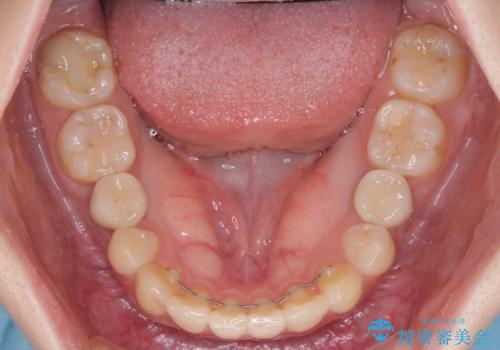

欠損と残存乳歯 矯正治療とインプラント治療

- 残存した乳歯や歯の欠損、歯並びを気にして来院された患者様です。

乳歯を残した状態は予後がよくないこと、矯正治療と補綴治療を総合的に進めていきたいとのことで、インビザラインによる矯正治療とインプラント補綴治療を並行して進めていくこととしました。

当院は矯正治療もインプラント補綴治療も、同一の歯科医師が担当するため、矯正治療を行いながら、最適なタイミングでインプラント補綴治療を行うことが可能です。

気になっていた部分がすべて解消され、患者様には大変満足していただきました。